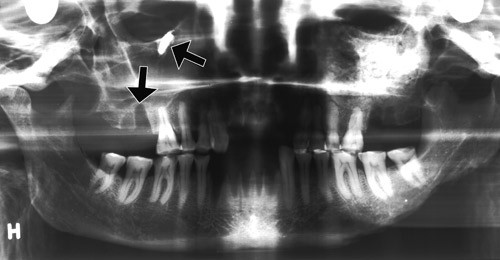

Bildet er fra en røntgenundersøkelse med ortopantomografisk teknikk av et middelalderkranium fra Oslo (De Schreinerske samlinger i Anatomisk institutt). Kraniet, fra en kvinne i alderen 40 – 60 år, har vært gravlagt ved kirken i Nonneseter kloster. Når hun levde, er ikke sikkert fastsatt. Klosteret omtales første gang i 1161 og synes å ha eksistert i flere tiår etter reformasjonen. Da Schweigaards gate ble opparbeidet i 1880-årene, «traf man saaledes flere skeletter, og i gadens nordre side 82 fod ifra dens sammenstød med Aaslo gade stod et hjørne af kvaderstene,» skrev antikvar Nicolaysen.

Overkjevens molarrøtter har nær anatomisk relasjon til sinus. Dette har stor klinisk betydning i odontologisk praksis. Bildet viser den nære forbindelsen mellom gulvet av sinus maxillaris, seksårsjekselen og den tomme alveolen etter tolvårsjekselen (pil). Høyt i sinus maxillaris, like under orbita, er det en tannrot «på avveier», dislokert til høyre sinus maxillaris (pil). Roten antas å stamme fra tolvårsjekselen.

Det er uklart hvordan tannroten har havnet i sinus maxillaris. Det kan være resultatet av hjemmebehandling som har ledet til aksidentell perforasjon. Middelalderens leger beskjeftiget seg ikke med tenner, og Kirken forbød på det strengeste tannekstraksjon – et inngrep som ble ansett å være farlig. Men det fantes flere «tannverkråd» som kanskje inspirerte til hardhendt egenbehandling i en fortvilet situasjon.

Røntgenbildet viser ellers avslipning av tyggeflatene (okklusal abrasjon), ingen caries og et friskt periodontium. Det skiller seg en del fra tilsvarende røntgenundersøkte kranier fra andre gravplasser i middelalderens Oslo. I de fleste er den okklusale abrasjonen betydelig mer uttalt, og mange har mistet tenner som følge av marginal periodontitt. Det er mulig at forskjellen i dental helse kan ha sammenheng med bedre kosthold i Nonneseter kloster enn i den øvrige befolkningen.